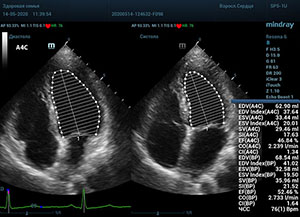

Что могут предложить современные приборы? Приборы нашего времени являются мощными вычислительными машинами, способными обрабатывать полученную информацию даже без помощи человека. Система автоматического вычисления фракции выброса – AUTO EF на приборах серии Resona компании Mindray сделает все за вас. За пару секунд прибор сам отыщет нужную фазу сердечного цикла и произведёт измерение и расчеты, а также покажет график изменения объема в сердечном цикле. От Вас требуется только получить качественное 4С и 2С сечение. Впрочем, прибор всегда оставляет возможность коррекции, если доктор имеет свое мнение на расположение точек планиметрии или момента измерения по ЭКГ каналу.